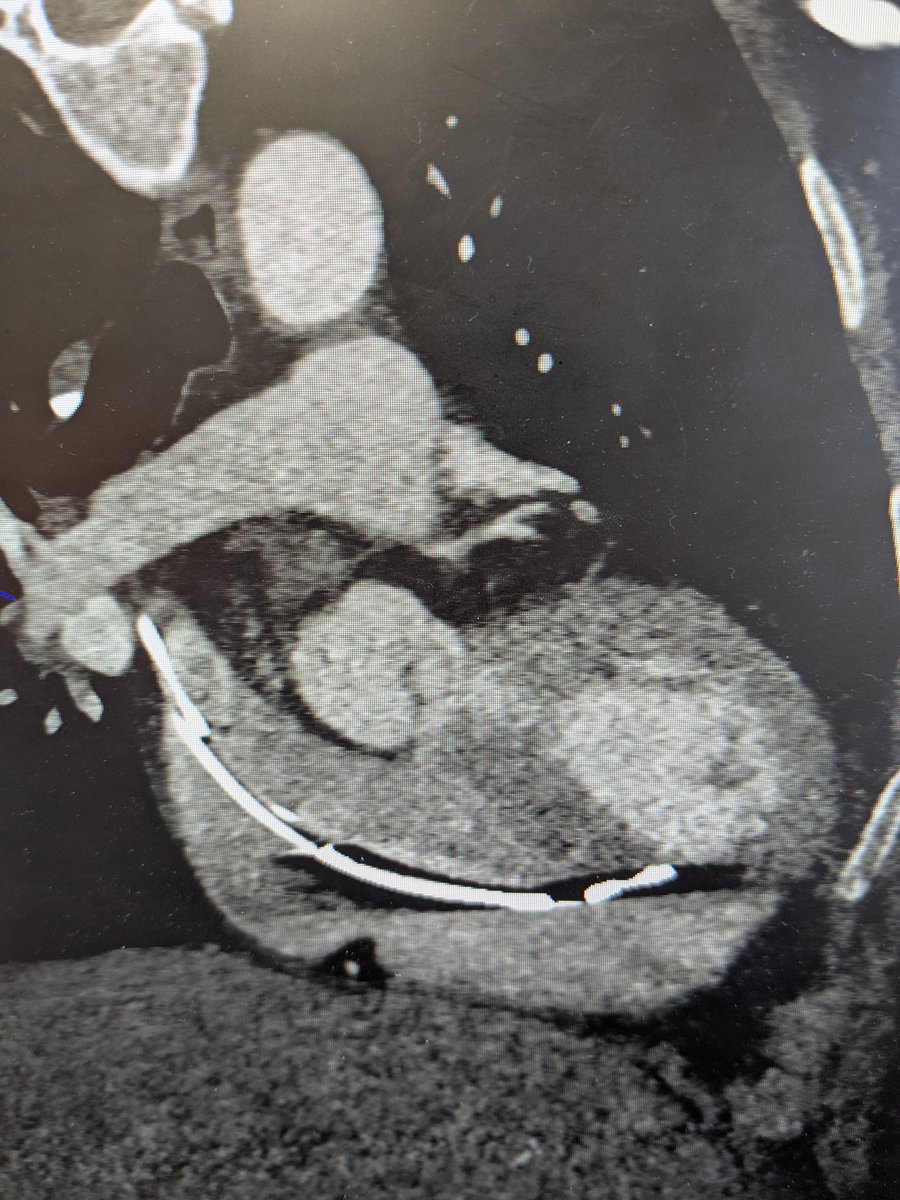

Our first *3* implants in the @AbbottCardio #ASCEND trial yesterday! The lead handles beautifully and we got fantastic LBB capture in all patients. #EPeeps #DontShocktheHis 😂😂